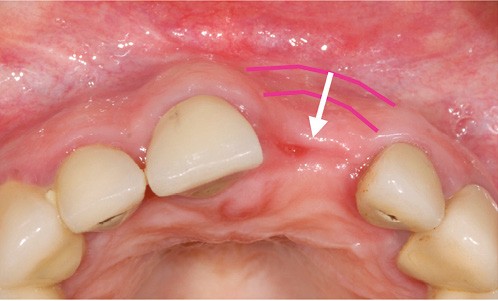

Lorsque la crête est déjà édentée, la résorption osseuse a déjà eu lieu et, en conséquence, la morphologie des tissus mous est altérée (fig. 1). Il faut alors utiliser des techniques d’augmentation osseuse et/ou muqueuse afin d’obtenir une architecture des tissus mous la plus naturelle possible.

L’architecture des tissus doit se visualiser en trois dimensions et comprend deux zones : la zone des papilles et celle de la gencive marginale, avec leurs composantes verticales, horizontales et la profondeur. L’autre aspect de cette architecture est lié aux types de tissus mous (muqueuse alvéolaire…